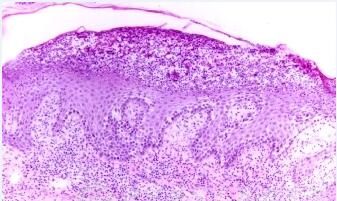

(5)银屑病。